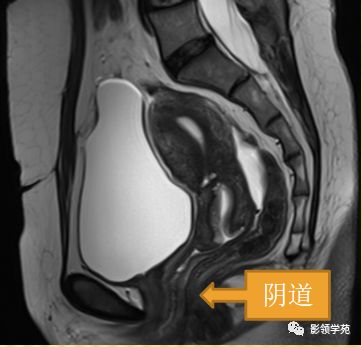

阴道壁

阴道粘膜 为复层鳞 状上皮

T1WI 呈中等稍低信号

T2WI内带:高信号(上皮、粘液)

外带 :低信号